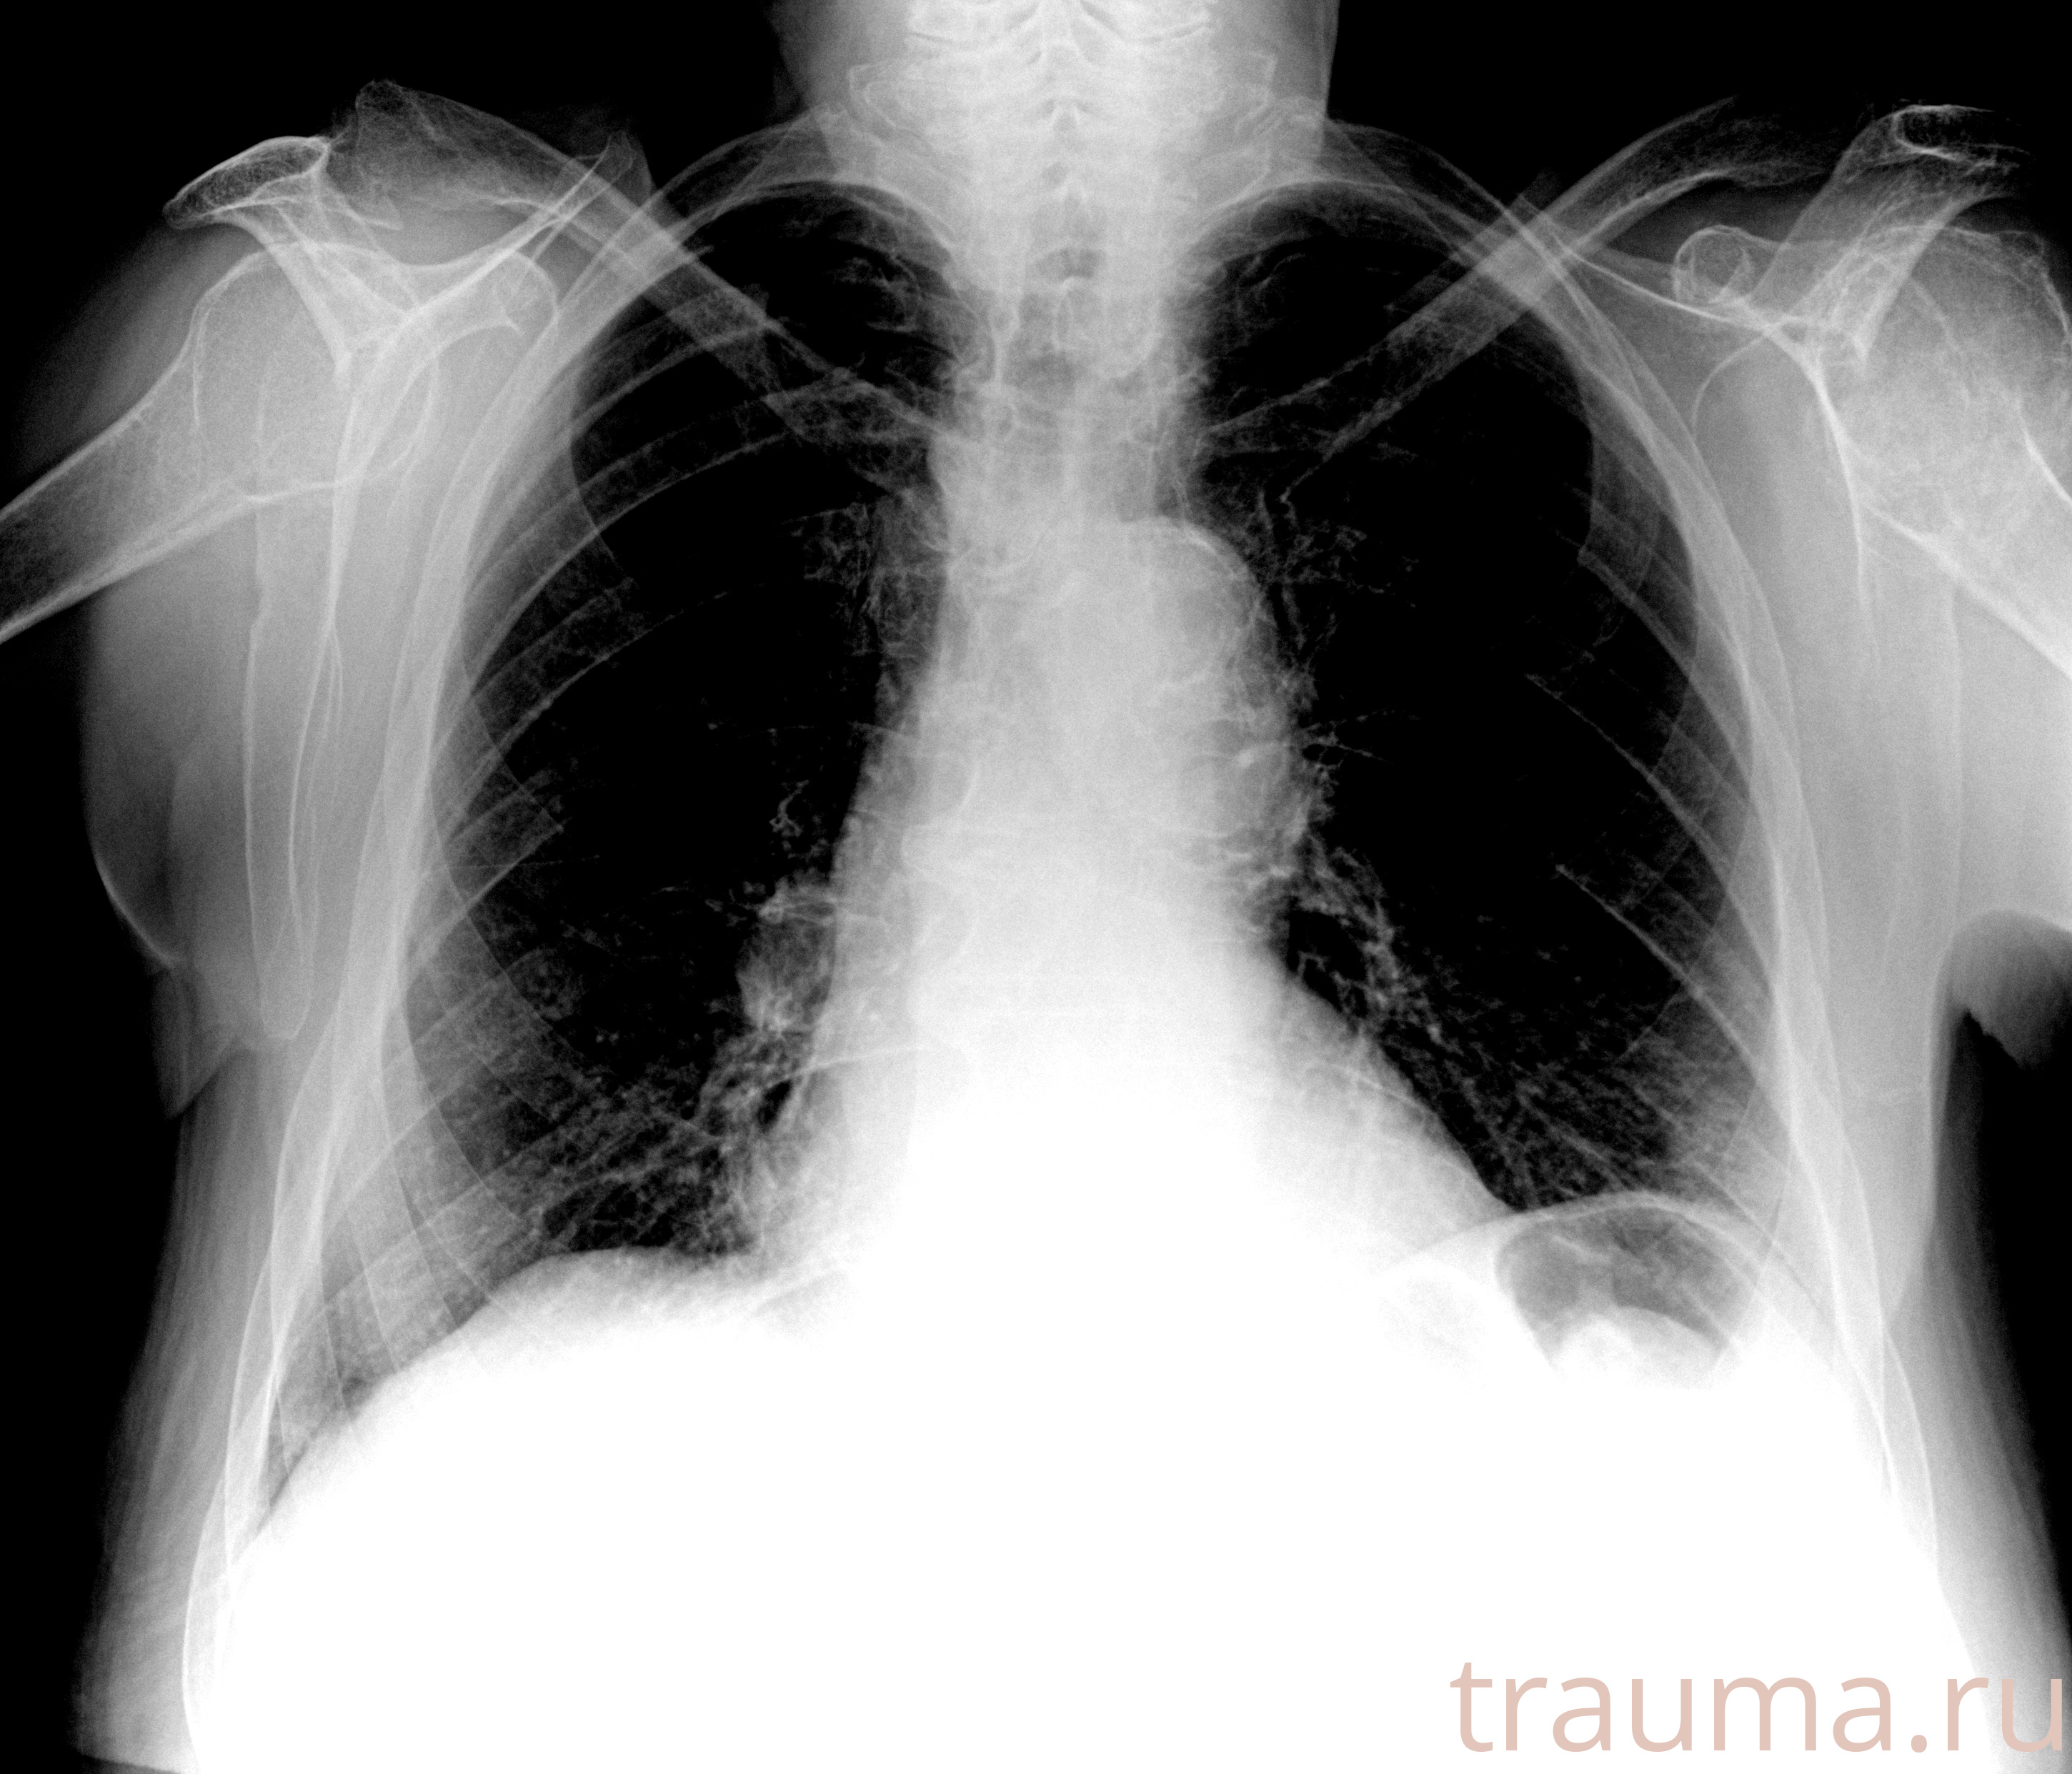

Рентгенограммы

Рентген на дому: по вашему адресу приезжает врач-рентгенолог, травматолог-ортопед с мобильным рентгеновским аппаратом, проводит диагностику травмы или заболевания, делает необходимые рентгенограммы, дает рекомендации по дальнейшему лечению. Получить качественные снимки в домашних условиях возможно благодаря уникальной методике, разработанной МосРентген Центром для института  Склифосовского